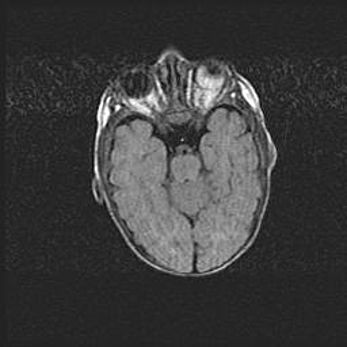

Сообщающаяся гидроцефалия. Кистозная энцефаломаляция головного мозга.

Возраст: 3 месяца 4 дня

Вес: 3100 г

Пол: женский

Окружность головы: 34 см

Срок гестации: 31 неделя

Кистозная энцефаломаляция головного мозга - одна из форм поражения головного мозга в детском возрасте. Характеризуется возникновением множественных и распространённых кист в коре, белом веществе и подкорковых образованиях головного мозга у плодов, новорождённых и детей раннего возраста. Развитие кистозной энцефаломаляции связано с внутриутробной асфиксией и гипотонией, родовой травмой, тромбозом синусов, пороками развития сосудов, инфекциями, сепсисом и другими причинами. Наиболее значимые инфекционные агенты: вирусы простого герпеса, цитомегалии, краснухи, токсоплазмы, энтеробактерии, золотистый стафилококк и другие.